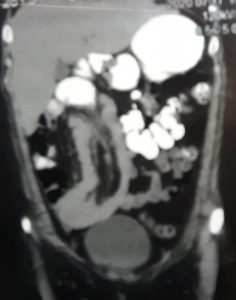

إستخدام المنظار الجراحي لعلاج إنسداد بالأمعاء الدقيقة نتيجة إنغماد جزء من الأمعاء الدقيقة(الصائم) في جزء آخر

Laparoscopic surgery for Jejuno-Jejunal intussusception